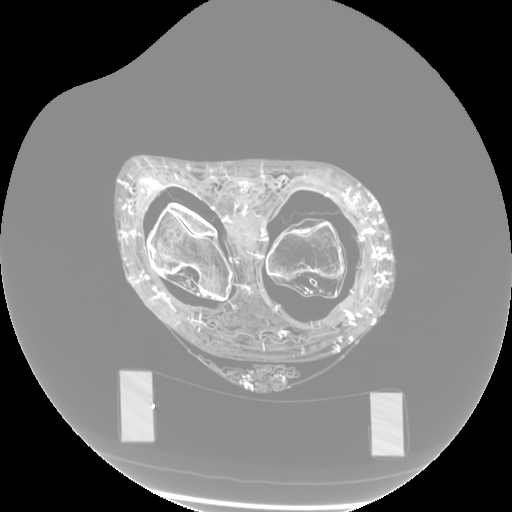

Figure 3: Visualization of axial frames of a mummy [6] selected in proximity of the thigh. (a) Some of the regions we are interested to segment are indicated. (b) Artifacts caused by presence of metals.

In Fig. 3a, we show one axial slice of a male mummy with indication of the regions to be segmented. Fig. 3b illustrates that metals present inside a bandaged mummy generate severe artifacts, which are not present in standard biomedical data.

In Fig. 6, we illustrate the described process using a synthetic image and a real axial frame. Note that in most slices, there exists an interior hollow space between the wrapping Bandage and Body. Detection of this region is trivial since its voxel values are the same as the air voxels in the detected exterior region. In practice, the obtained set RbsubscriptR𝑏\mathrm{R}_{b} may also include some patches from the wrap region in addition to the body patches. In the next section, we refine this result.